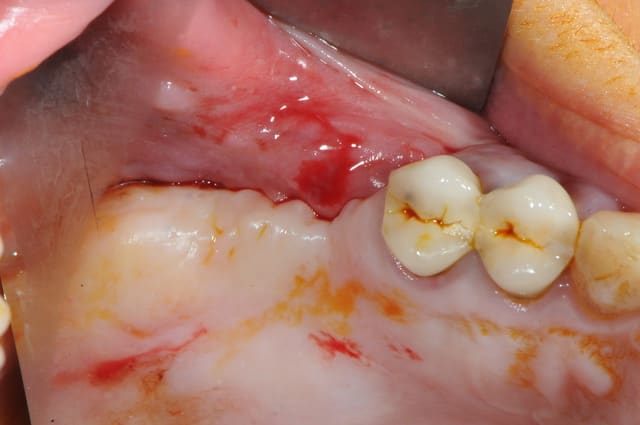

rhizalyse

je dois pratiquer un rehaussement de plancher sinusien par volet latéral et je ne sais comment gérer le décollement de la membrane de Schneider au niveau de la communication bucco sinusale

Dès le départ, je m'inquiète au niveau du décollement du lambeau sur la CBS, on risque de déchirer à ce moment là

je joins quelques captures pour vous faire une idée